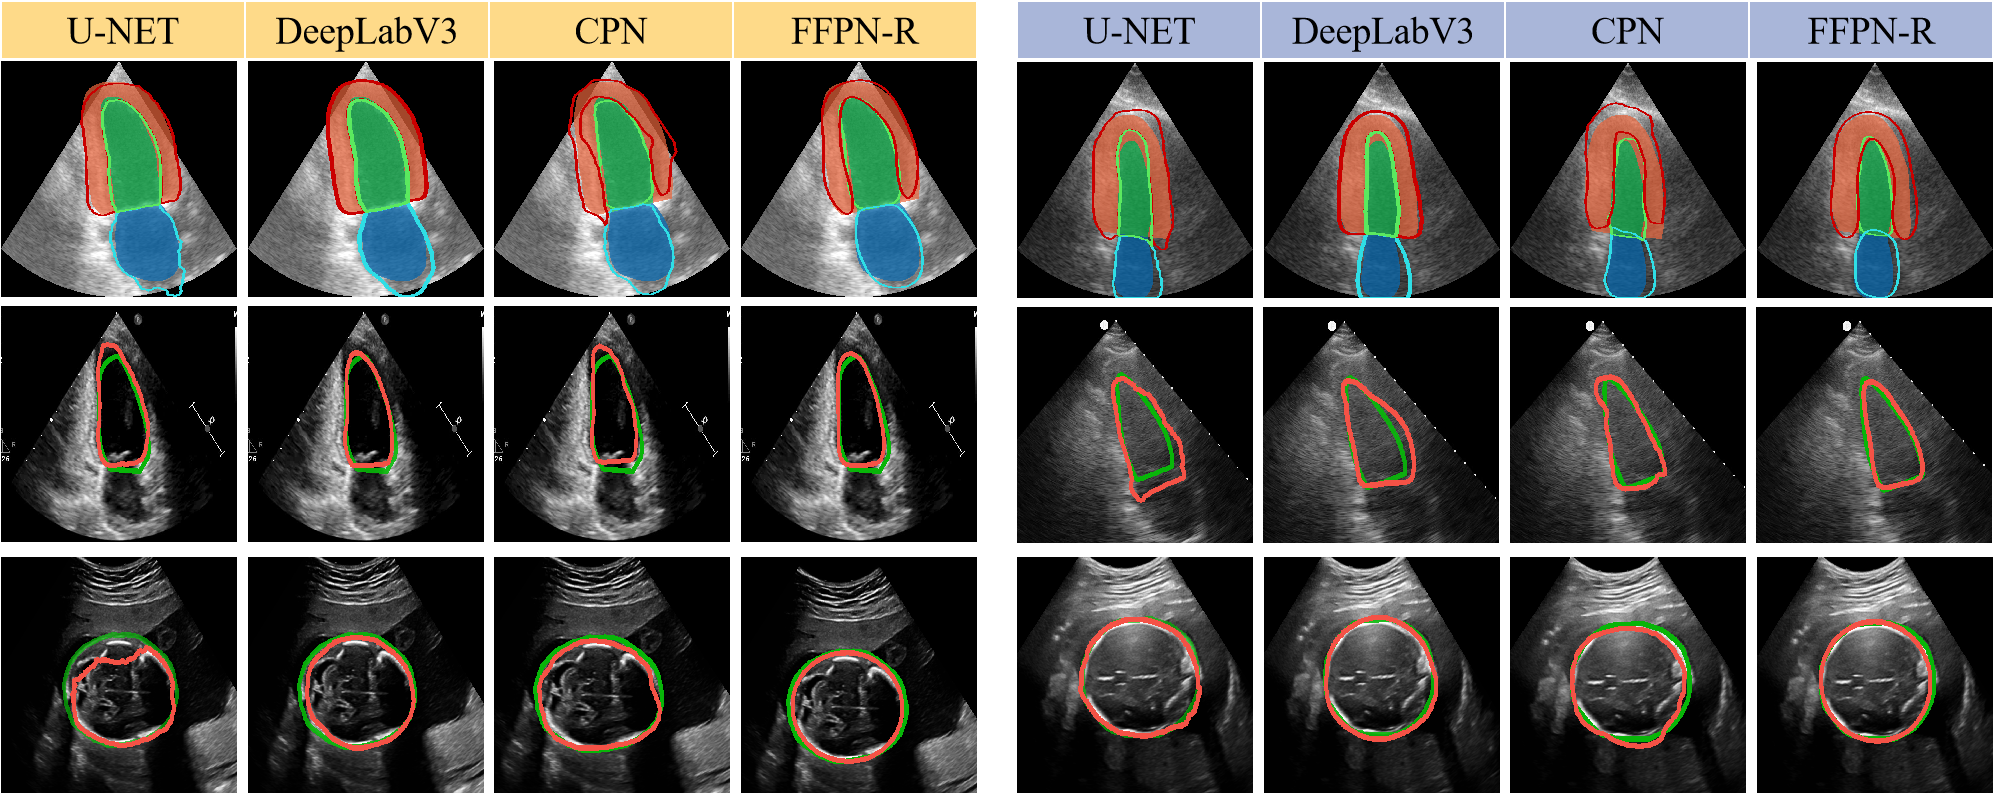

In addition, we have also validated the effectiveness of our framework in the multi-class segmentation task. As shown in Table 2, FFPN-R achieves a more significant improvement on the Camus dataset compared to other DTS approaches, as compared to the single-class segmentation tasks. This further illustrates the generalizability and scalability of our framework. On the Camus dataset, FFPN-R outperforms most Pixel-based methods. However, the wrapping of the myocardium around the left ventricle poses a challenge in accurately assigning positive and negative samples within the detection framework, resulting in our results being slightly inferior to DeeplabV3. Fig. 5 shows the segmentation results of U-NET, DeepLab V3, CPN and FFPN-R. It demonstrates the superior performance of FFPN-R on the segmentation task in US images.

Figure 5: Segmentation results of different methods on three datasets. For the first row (Camus), the masks are ground truth, and the contours are predictions. For the second (2CH) and third row (FH), the green contours denote ground truth, and the red contours represent predictions.